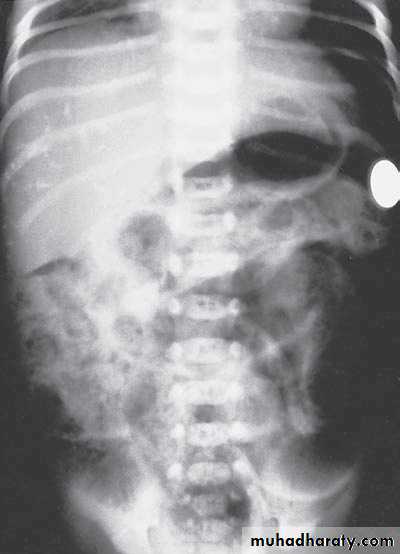

Bowel Obstruction